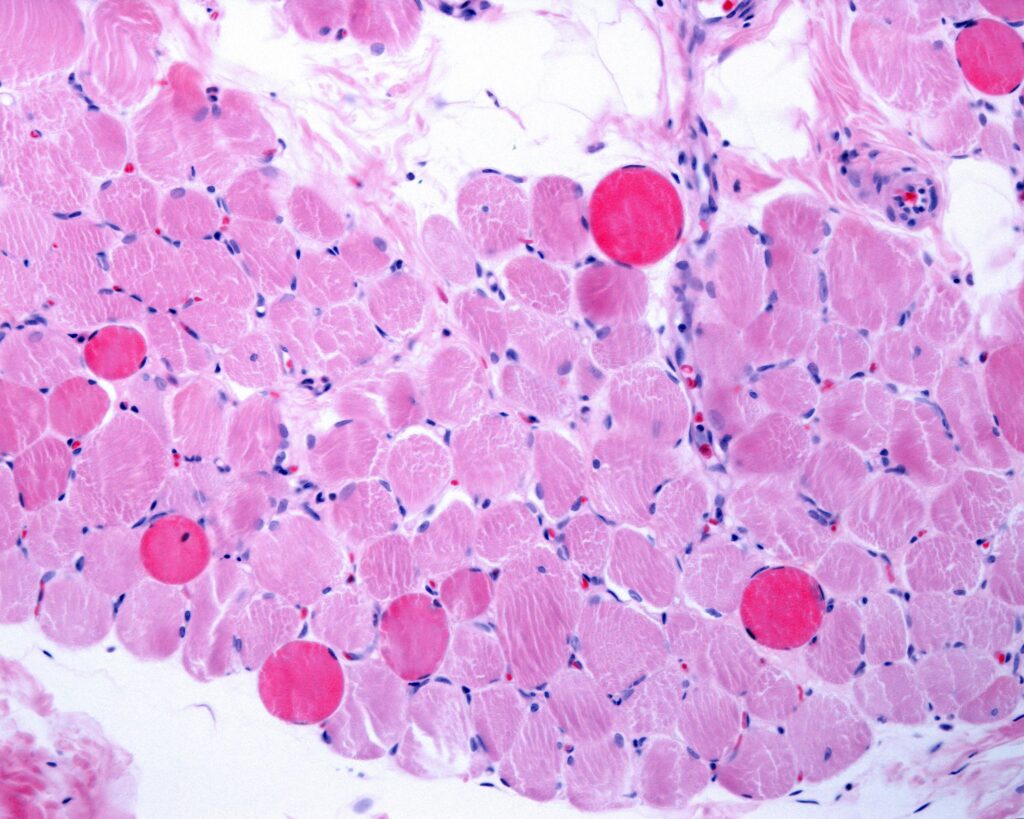

« Résoudre l'inflammation dans le contexte des dystrophies musculaires est l'un des défis les plus redoutables que les chercheurs et les cliniciens cherchent à résoudre », explique Villa. Les scientifiques ont trouvé un moyen de « diriger » des exosomes modifiés ayant une action anti-inflammatoire dans les muscles malades : en utilisant des nanotubes ferromagnétiques comme support, ces exosomes peuvent migrer spécifiquement dans les muscles endommagés par la dystrophie musculaire de Duchenne (DMD) grâce à l'application d'un champ magnétique externe. après une injection systémique. « Nous avons réussi à contrôler la biodistribution et le ciblage des exosomes in vivo afin de réduire l'état inflammatoire des muscles touchés par la DMD », souligne Villa. Des analyses quantitatives au niveau musculaire ont montré que les macrophages, un type de globules blancs, dominent l'absorption des exosomes injectés, favorisant la régénération musculaire et améliorant les performances musculaires dans un modèle murin de dystrophie de Duchenne.